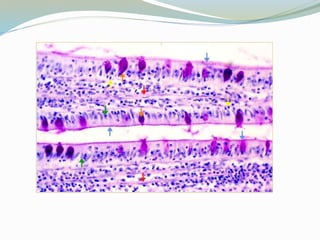

 Absorven lípidos: Los lípidos primero son captados por las

miscelas intraluminales de sales biliares, que los estabilizan

en una emulsión y los transportan al borde estriado donde

difunden al interior de la célula como ácidos grasos

 Estos ácidos se unen a un componente glucoproteínico

(apoproteína) en el retículo de golgi

 Las gotitas de quilomicrones de lipoproteína así formados

pasan hacia los espacios intercelulares y se dirigen hacia

abajo para atravezar la lámina basal y entrar a los vasos

linfáticos (quilíferos), de la lámina propia

Células de Paneth

 Son células secretorias de proteína, la secreción se

acelera después de los alimentos

 Son capaces de fagocitar bacterias